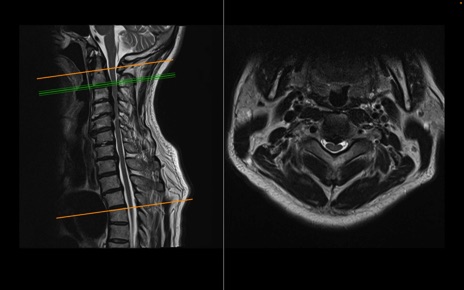

頚椎MRI

T2WI(横断像)

T2WI(矢状断像)